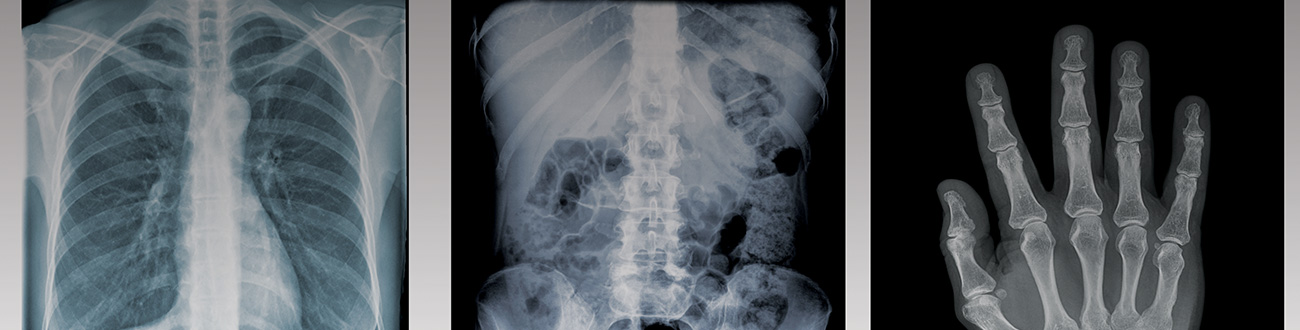

Radiologic Technology is a science combining advanced technology and human compassion. Radiologic technologists use their knowledge of physics, human anatomy and physiology to create permanent medical images for the diagnosis of disease.